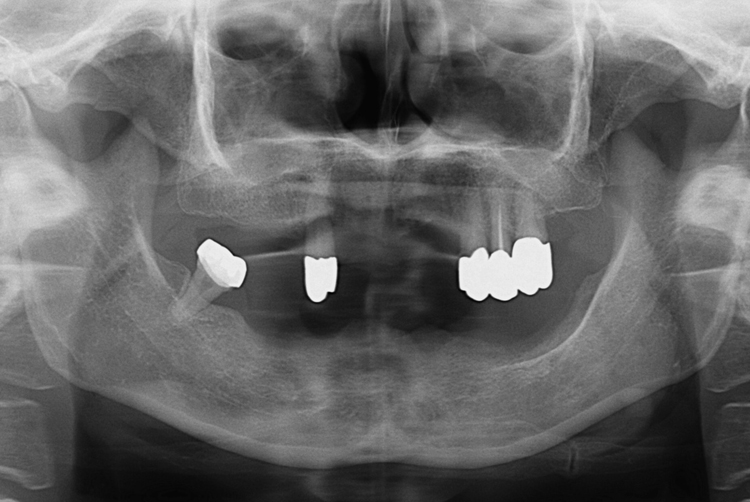

치료사례

세종치과의 진심 어린 치료는 결과로 말합니다.

실제 내원하신 환자분들의 치료 전·후 사례를 확인해보세요.

모든 치료사례 전후사진은 환자분의 동의하에 촬영되었습니다.

모든사진은 동일 환자분의 전후모습을 촬영하였으며, 사진의 밝기조절 외에 임의 수정이 없음을 알려드립니다.